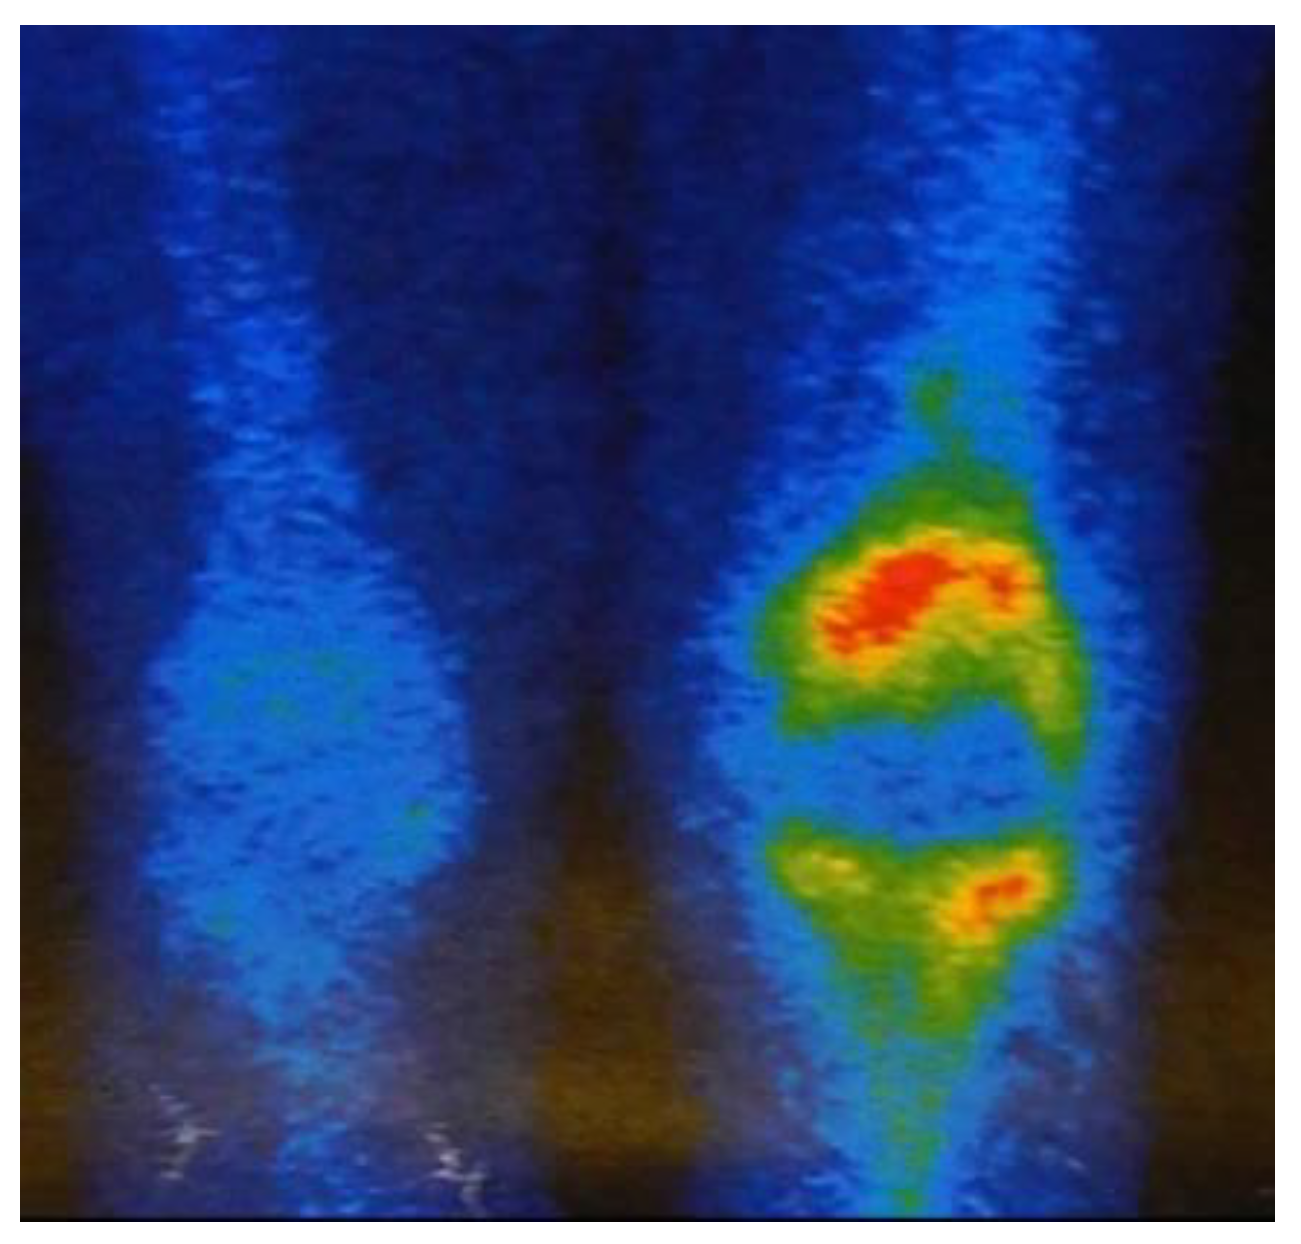

The microorganisms responsible for the knee infections (Figure 3) varied widely and included 4 cases of methicillin resistant Staphylococcus aureus (MRSA), 2 cases of vancomycin-resistant Enterococcus, and 2 cases of multi-organism infections.

Figure 3.

Bone scintigraphy showed an increase in Tc-99 uptake in the left knee joint.